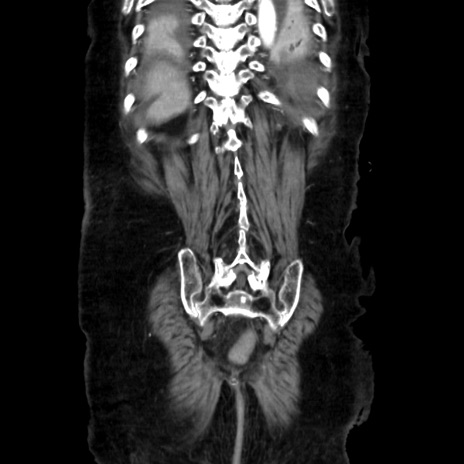

症例40(冠状断像)

冠状断像